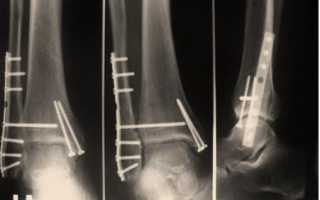

Остеосинтез

При переломе лодыжки часто повреждаются связки и структура «вилки» голеностопного сустава, которая ограничивает его с обеих сторон. Это создает необходимость в восстановлении целостности «вилки», то есть концов малоберцовой и большеберцовой костей, которые формируют сустав голеностопа, а также в их последующей фиксации с помощью остеосинтеза.

В зависимости от степени сложности перелома щиколотки применяются различные методы остеосинтеза:

Закрытый метод остеосинтеза включает использование специального оборудования, которое, под контролем рентгена, перемещает отломки кости на их естественное место для последующего сращения. Для этого в области перелома устанавливаются спицы из прочного металла, которые затем соединяются со скобами компрессионно-дистракционного аппарата. Это устройство называется аппаратом Илизарова. Данный метод чаще всего применяется при менее сложных травмах.

Проведение открытого остеосинтеза

Оптимально проводить операцию в кратчайшие сроки после травмы, особенно в случае открытого перелома, так как существует высокий риск микробного заражения, что может привести к осложнениям и гангрене. Открытый метод остеосинтеза позволяет более эффективно сопоставить отломки кости, удалить поврежденные элементы и освободить мягкие ткани, зажатые между костными фрагментами. Затем осуществляется грубая фиксация с использованием пластины с несколькими отверстиями и винтов. Для достижения максимальной эффективности фиксации специалисты заранее моделируют форму пластины, подходящую к поврежденной кости, и только после этого фиксируют пластину винтами, чтобы избежать повреждения структуры голеностопного сустава. Пластина удаляется после полного сращивания переломанной кости.